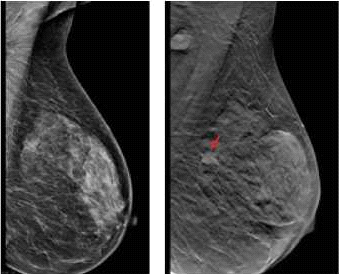

דוגמה לכך ניתן לראות בתמונות 1-4 בהן נראית רקמת שד צפופה (ללא גורמי סיכון נוספים), כפי שהיא משתקפת בממוגרפיה. בבדיקה זו לא נראה ממצא חשוד, אך בבדיקת האולטרסאונד נמצאה קרצינומה בגודל של 0.7 ס"מ (סנטימטר) בשד שמאל, ברביע החיצוני העליון. אותו ממצא נראה גם ב-MRI. לעומת זאת, תמונה מספר 5 היא דוגמה של בדיקת ממוגרפיה בה נראית קרצינומה על רקע של רקמת שד שומנית, עובדה המקלה על גילוי גידול מסוג זה.